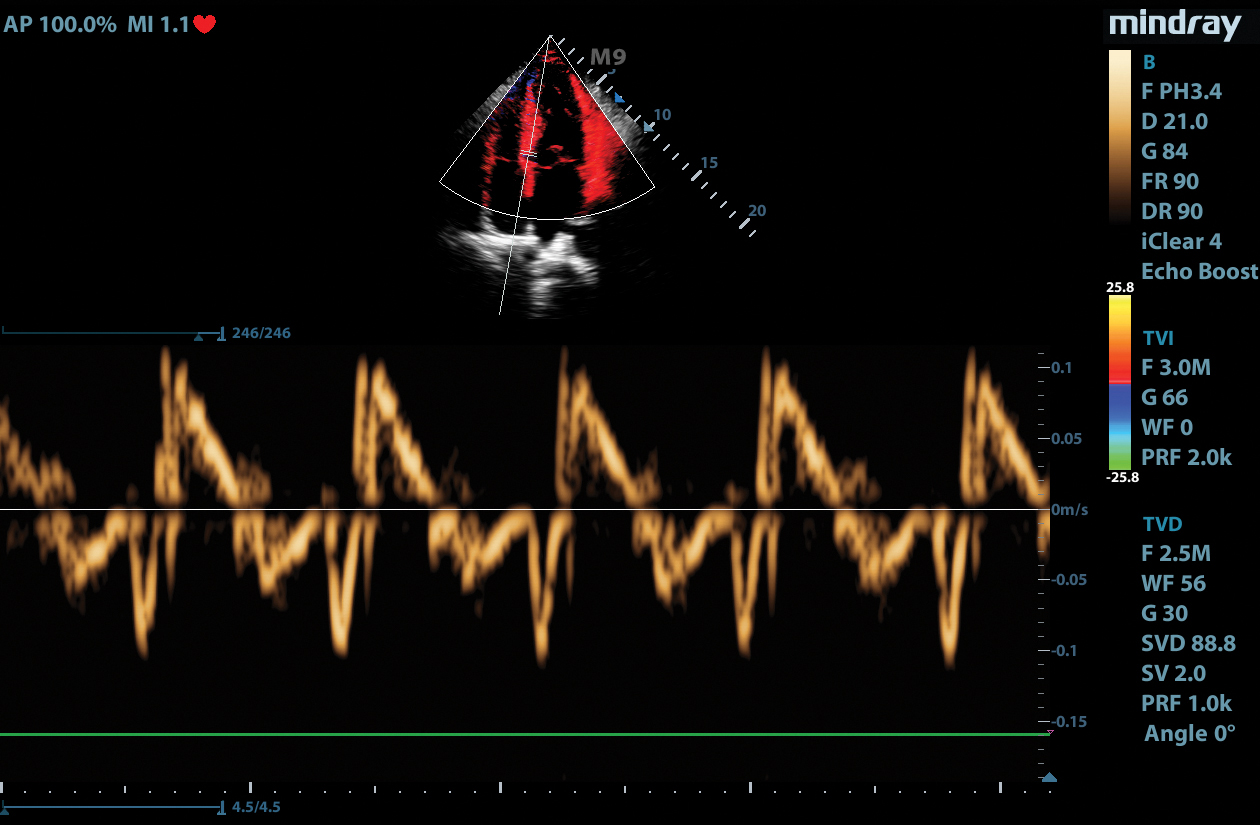

Tissue Tracking

Mindray’s Tissue Tracking technology with quantitative analysis allows users to monitor the displacement of cardiac tissue by tracking the speckle displacement in the image from frame to frame. This non-angle dependent tool with onboard analysis, can be performed at the bedside, saving time and simplifying challenging cases.